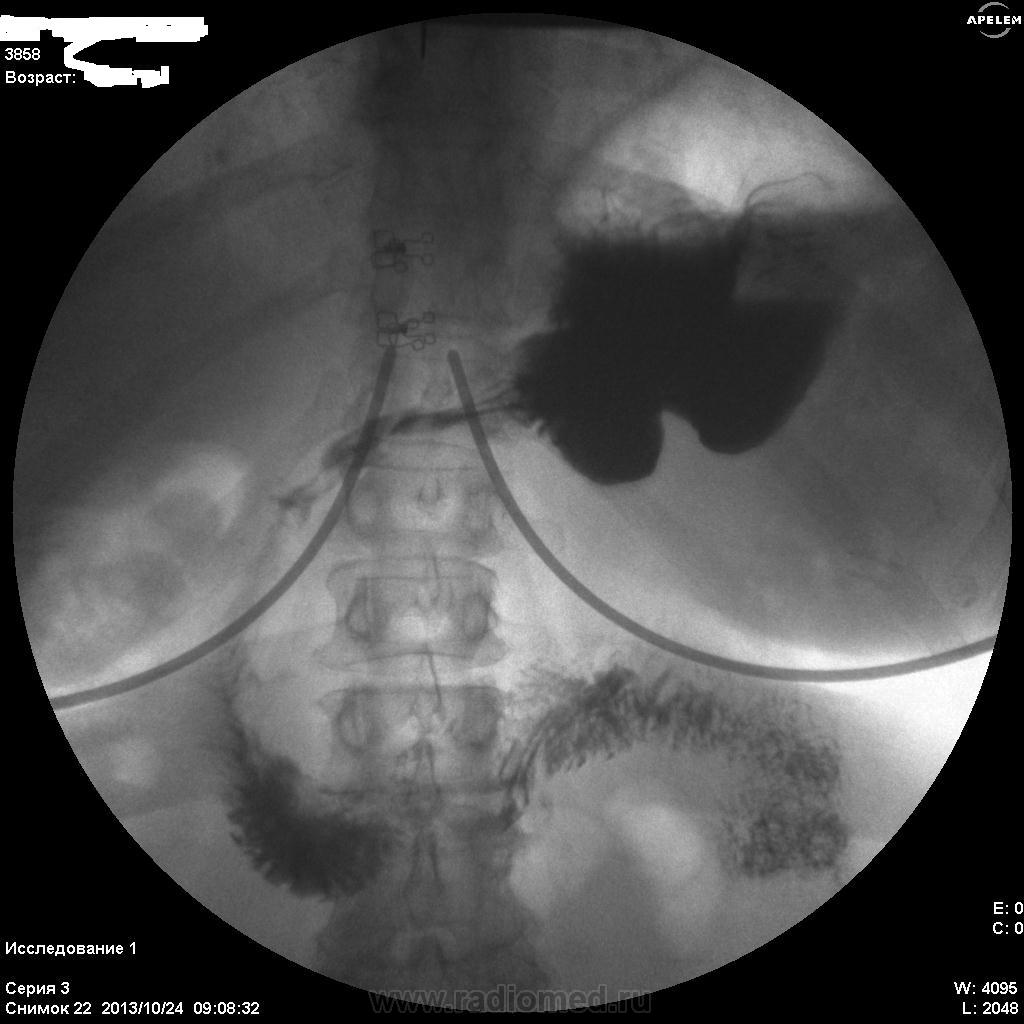

Необходимо уточнять состояние большой кривизны субкардиального отдела и тела (новообразование?), только ЭТИХ снимков явно мало...увы....

По-желудку - расположен косопоперечно, в гипертонусе. Впечатление не полного тугого наполнения. На большой кривизне могут быть и складки, плохо видно. На малой кривизне похоже на 2 ниши, ширина которых преобладает над глубыной, могут быть онкологические, но опять же куда они деваются на последнем снимке... Пилорический отдел либо конически сужен, либо не наполнен адекватно. В общем, можно просто предположить, либо это язвеная болезнь "хроническая" (отсюда деформация желудка и все остальное), либо это онкология (лимфома к примеру). Либо вообще такую картину дает гипертонус, усиленная перистальтика и малое количество контраста. Предложил бы искусственную гипотонию и бария не менее 200 мл.

Первые три-в орто.Последний-лёжа.

А поджелудочная (головка), так скиалогически далека от нормальности.